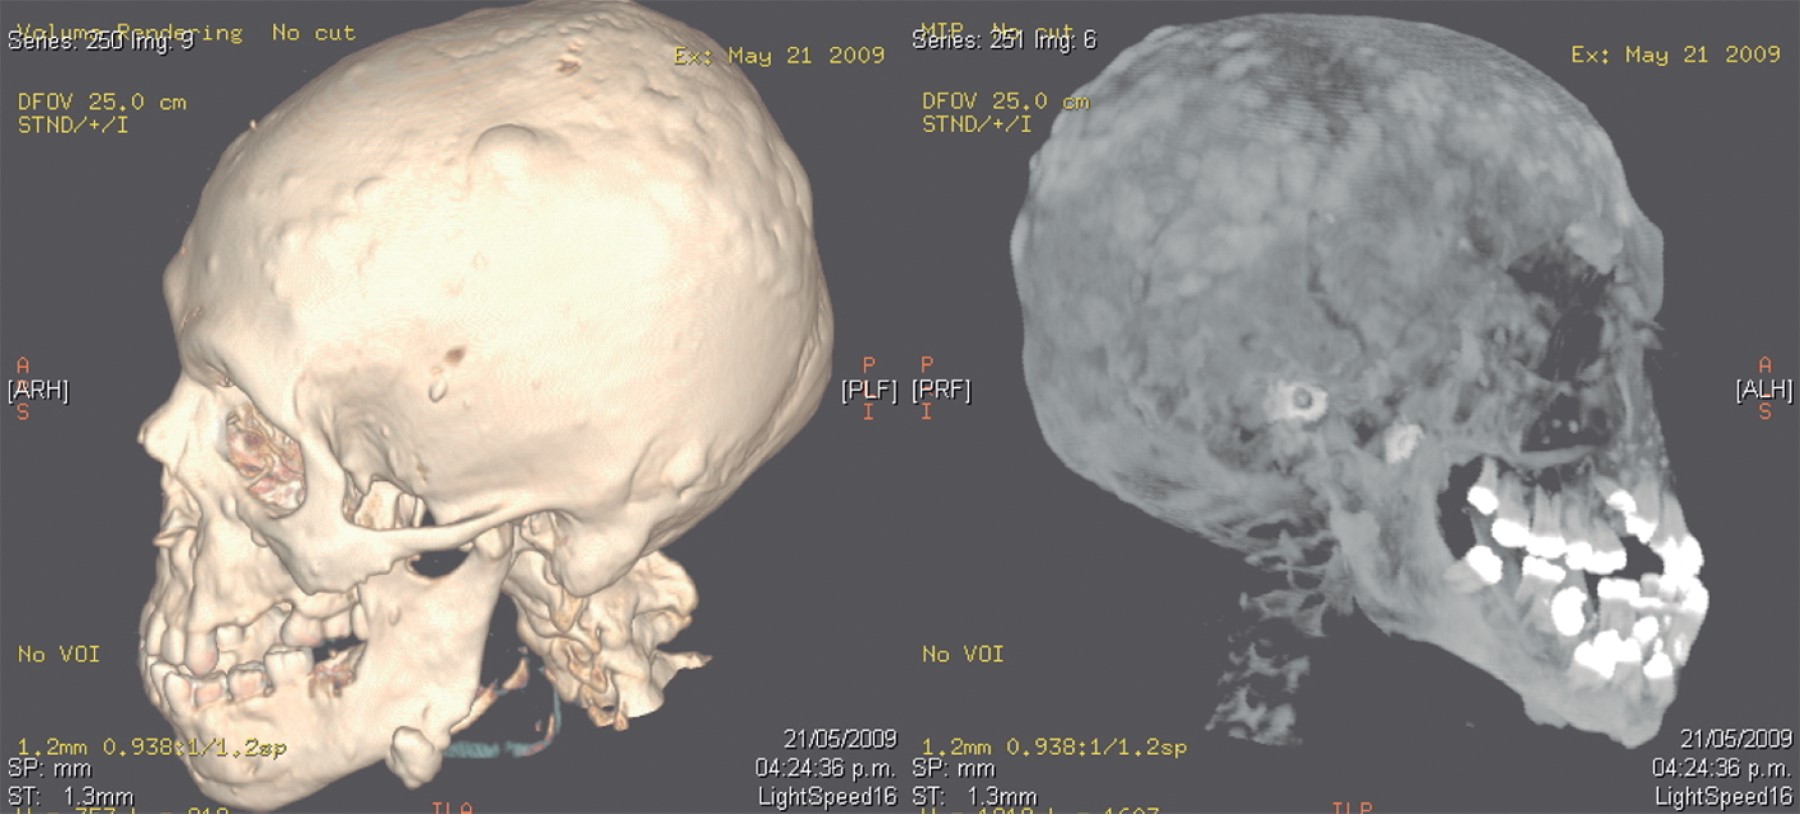

Las características clínicas dentales y maxilofaciales que presentaba alertaron a los clínicos sobre un posible síndrome de Gardner, confirmándose mediante una tomografía 3D, en la cual se observan con claridad múltiples exostosis craneofaciales (osteomas) (Figura 3).

Si bien los osteomas pueden desarrollarse ocasionalmente en cualquier parte del esqueleto, aparecen casi exclusivamente en la región craneofacial, manifestándose tanto en el maxilar como en la mandíbula (Figura 1); sin embargo, esta última tiende a afectarse más. Además, también suelen invadir los senos frontales, maxilares y etmoidales.4

Evidentemente, cualquier alteración que afecte a la densidad ósea presenta hallazgos radiográficos. Los osteomas se pueden apreciar de manera radiográfica como lesiones radioopacas bien definidas con una densidad aumentada a la del hueso sano.2

MANIFESTACIONES CRANEOFACIALES

Las alteraciones craneofaciales del síndrome de Gardner son sumamente características, pues el cráneo y los maxilares son los sitios principales donde se manifiestan los osteomas, lesiones osteogénicas benignas de crecimiento lento que pueden desarrollarse en hueso compacto,7 trabecular y mixto y que comienzan a desarrollarse durante la pubertad.